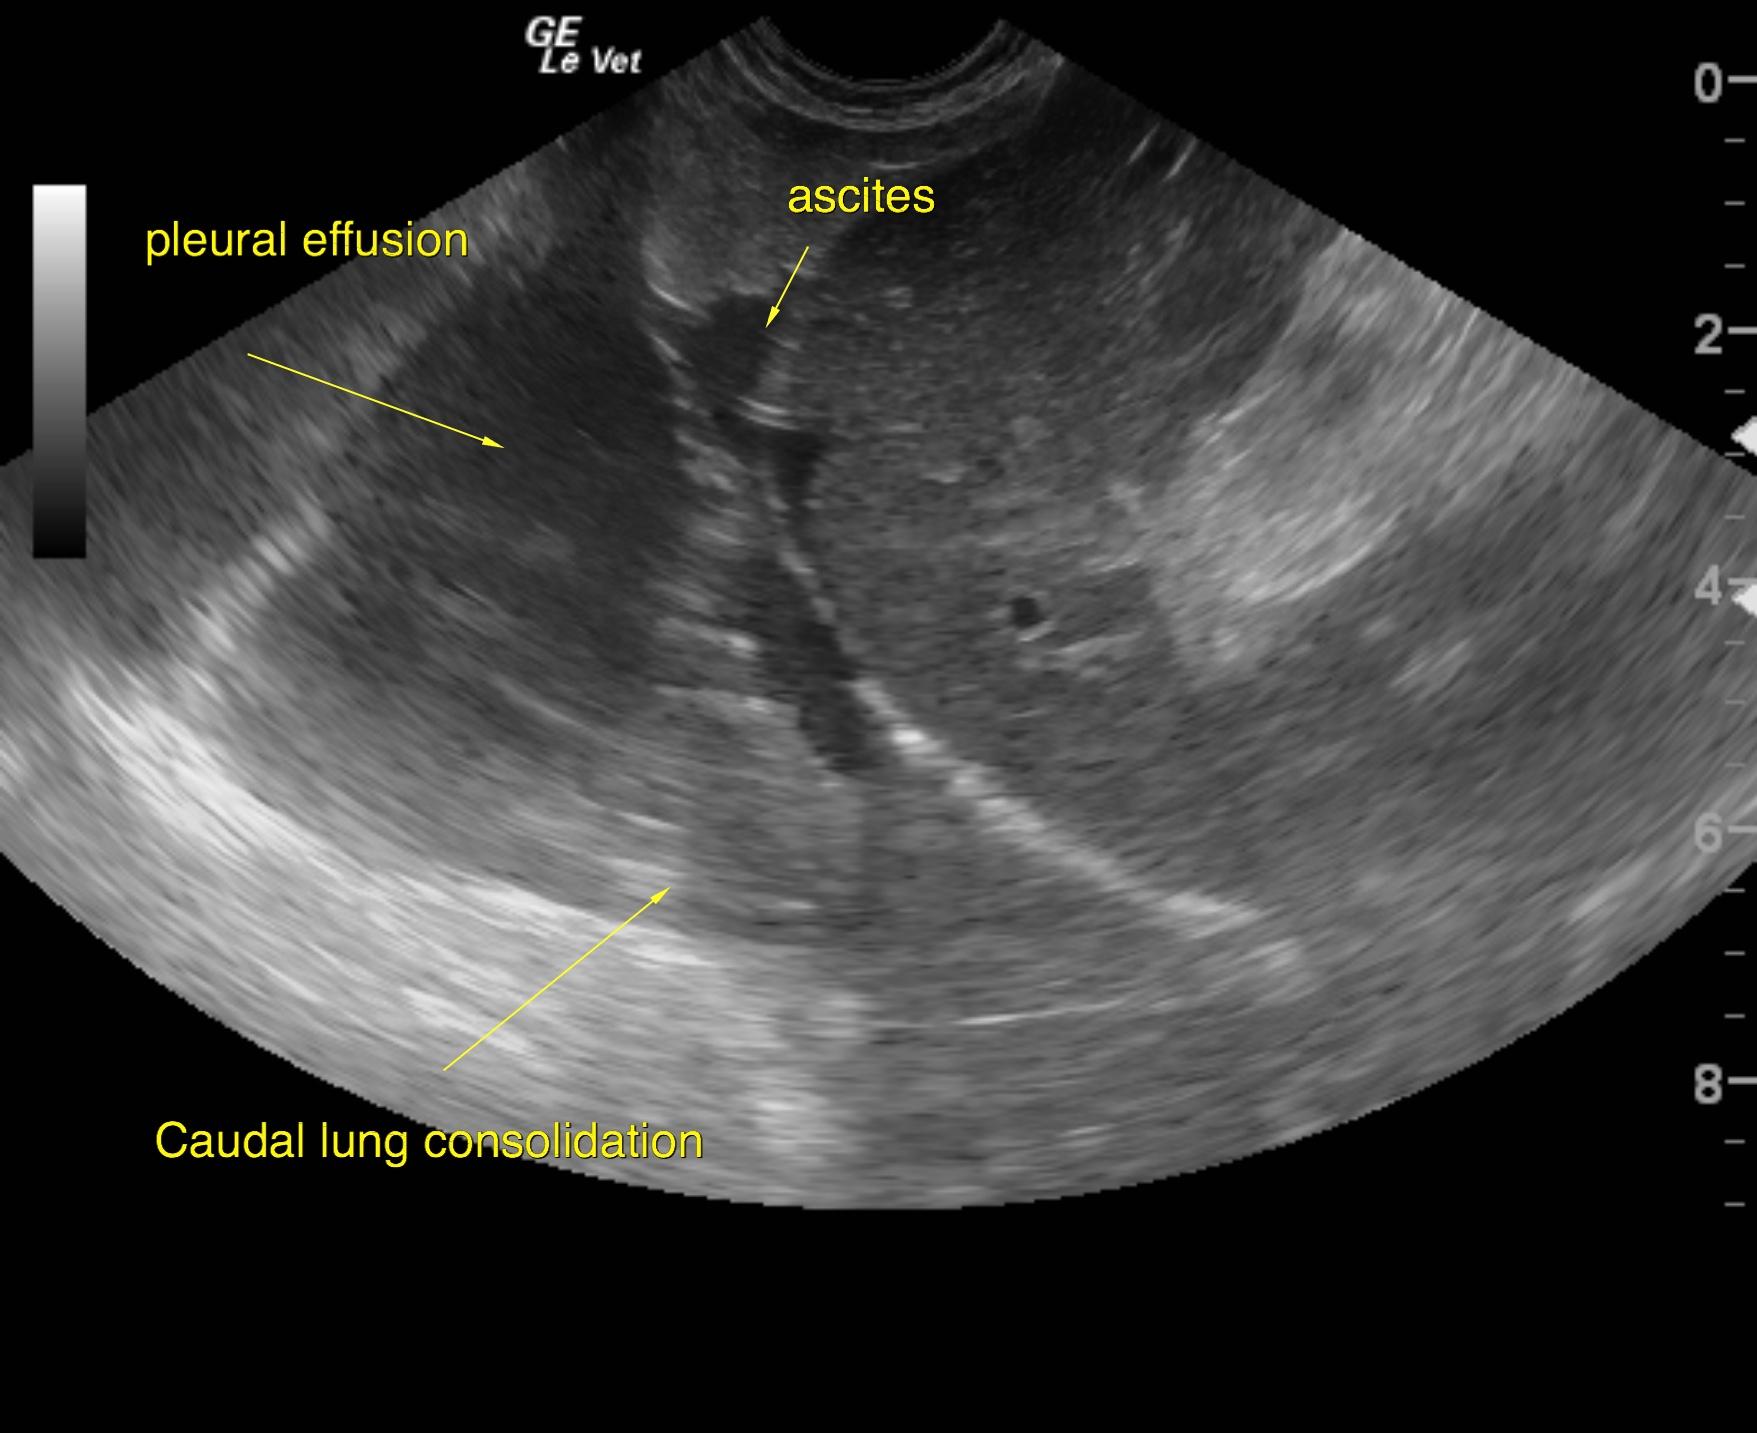

A 10-year-old NM Pomeranian was presented for evaluation of decreased appetite, increased respiratory rate and effort, abdominal distention, and syncopal episodes for the past two weeks. Abnormalities on physical examination were Grade V/VI heart murmur, clear lungs with increased respiratory rate and effort, a palpable fluid wave. Urinalysis showed 3+ proteinuria. Abnormalities on CBC and serum biochemistry were leukocytosis and hypoproteinemia. Survey radiographs showed mild pleural effusion, severe cardiomegaly, and decreased serosal detail within the abdomen.